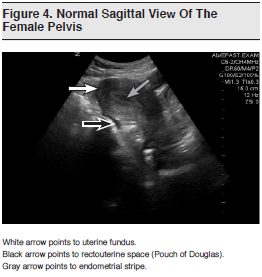

Transabdominal ultrasound can identify an IUP in most women at 6 or 7 weeks’ gestation, while TVUS can identify an IUP 7 to 14 days earlier, at 5 to 6 weeks’ gestation.44 While TVUS scanning provides superior imaging of the uterus (ie, retroverted uterus) and adnexa, TAUS ultrasound offers a more global view of the pelvis, is easier to learn, and requires less maintenance from an infection-control perspective.34 (See Figure 4) For emergency clinicians, sonographic findings consistent with an IUP include a yolk sac, fetal pole, or fetal heart activity within the uterus, surrounded by an 8-mm rim of myometrium. (See Figure 5) Visualization of a yolk sac, whether by TAUS or TVUS, is the first definitive evidence of an IUP. Once an IUP has been confirmed, fetal viability (fetal heart rate) and gestational age can also be determined. Although visualization of an IUP does not completely exclude ectopic or heterotopic pregnancy, its presence — in patients without risk factors — decreases the chances sufficiently to allow for further outpatient management.34,38

Direct visualization of an ectopic pregnancy can be challenging, and is even more so when TVUS is not performed, since the most frequent finding in ectopic pregnancy is a complex adnexal mass.42 Although the emergency clinician may directly visualize an ectopic pregnancy, the focus of the scan is on assessing for an IUP (or lack thereof) or for the presence of free fluid in the hepatorenal space (Morison’s pouch) or the pelvic space (Pouch of Douglas). Transabdominal views of the right upper quadrant and pelvis are integral to ultrasound imaging of the symptomatic first-trimester pregnant patient. Although the presence of significant intraperitoneal fluid in a pregnant patient without a definite IUP is indirect evidence, it is suggestive of an ectopic pregnancy, and its detection can be life-saving.46